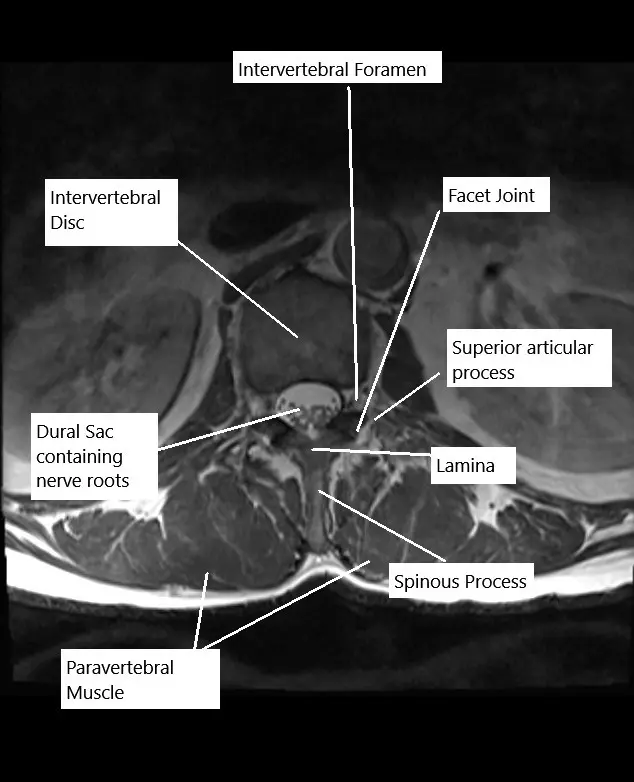

The lumbar spine consists of five vertebrae (L1-L5) and intervertebral discs that separate each vertebra. The spinal cord passes through the spinal canal, and spinal nerves exit through openings called foramina. These nerves control sensation and movement in the lower body, including the legs, feet, and pelvis. When discs herniate or the spinal canal narrows, it can compress the nerve roots, leading to pain and loss of function.

Microdiscectomy and laminectomy are both classified based on the type of surgery and approach:

- Microdiscectomy: Removal of herniated disc material to relieve nerve pressure.

- Laminectomy: Removal of part or all of the lamina (the back portion of the vertebra) to create more space in the spinal canal.